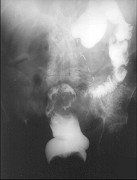

- 单项选择题女,50岁, 便血10余年,加重1年(连续出血), 近2个月大便时肛门常滴鲜血,量较多, X线检查如图,最可能的诊断为 ( )

E、直肠绒毛状腺瘤